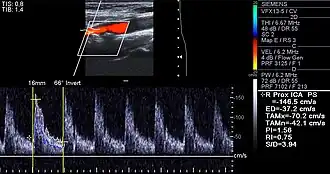

Carotid arteries supply blood to the brain and neck.[25] Marked narrowing of the carotid arteries can present with symptoms such as a feeling of weakness; being unable to think straight; difficulty speaking; dizziness; difficulty in walking or standing up straight; blurred vision; numbness of the face, arms and legs; severe headache; and loss of consciousness. These symptoms are also related to stroke (death of brain cells). Stroke is caused by marked narrowing or closure of arteries going to the brain; lack of adequate blood supply leads to the death of the cells of the affected tissue.[26]

Besides the traditional diagnostic methods such as angiography and stress-testing, other detection techniques have been developed in the past decades for earlier detection of atherosclerotic disease. Some of the detection approaches include anatomical detection and physiological measurement.

Examples of anatomical detection methods include coronary calcium scoring by CT, carotid IMT (intimal media thickness) measurement by ultrasound, and intravascular imaging techniques, such as intravascular ultrasound (IVUS), and intravascular optical coherence tomography (OCT),[85][86] allowing direct visualization of atherosclerotic plaques.